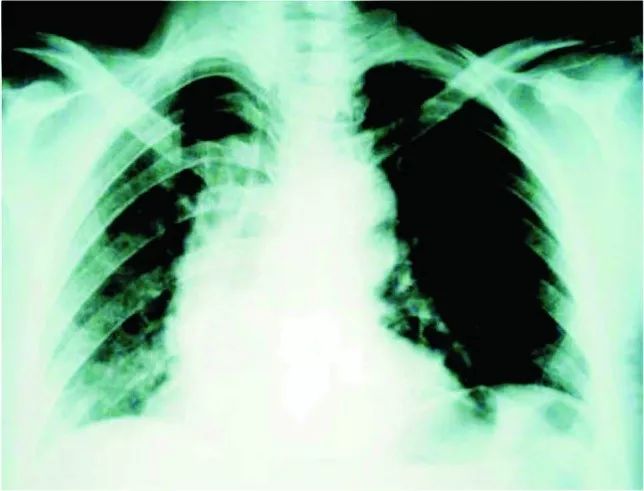

患者女性,41岁,因胸骨后疼痛2小时被送入急诊室。患者自述胸痛向肩胛间区放射,入院前几天一直有流涕、咽痛、咳嗽、呕吐。既往健康,无冠心病危险因素。

查体及常规实验室检查均正常,胸片显示右侧胸腔积液,无纵膈气肿和皮下气肿(图5)。心电图提示胸前导联ST段压低、T波倒置,超声心动图未见明显异常。入院6小时后复查心肌酶仍为正常,心电图无动态改变。实验室检查发现患者入院6小时的血红蛋白由130 g/L降至110 g/L。

图5 入院时胸片

患者恶心、呕吐加重,仍有持续胸痛。于是,进行了CT检查(图6),发现纵膈内少量积气、食管下段周围积液。患者接受了手术治疗,术后恢复良好。

图6 入院6小时后CT检查